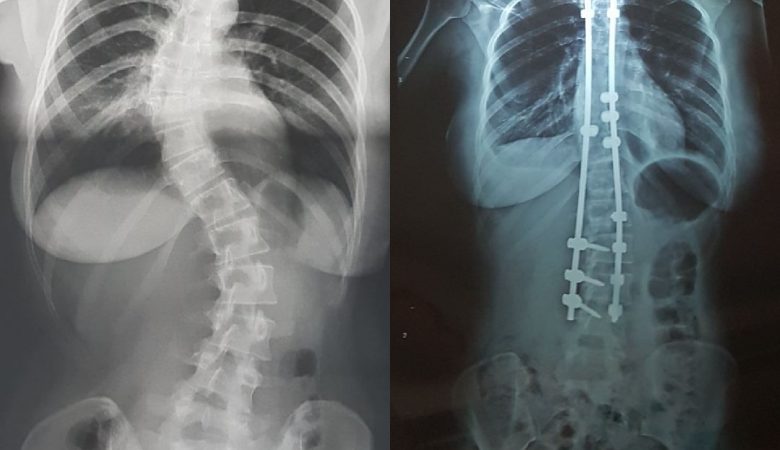

La scoliose est une déviation sinueuse de la colonne vertébrale dans les trois plans de l’espace: inclinaison dans le plan frontal, rotation des vertèbres dans le plan horizontal et inversion des courbures dans le plan sagittal. Il s’agit d’une déformation non réductible, contrairement à l’attitude scoliotique. Une déviation du rachis est considérée comme une scoliose …